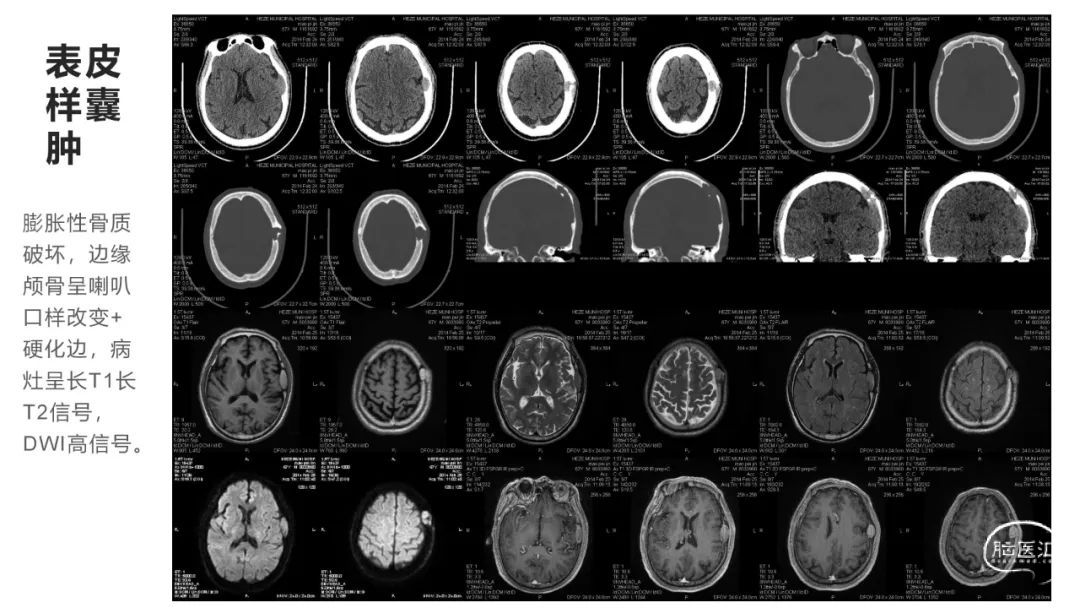

颅脑影像诊断基础知识讲座:颅骨病变